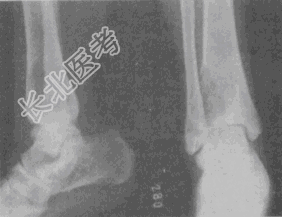

- 单项选择题女性,22岁, 小腿疼痛2个月。X线片和CT片如图。应首先考虑的诊断是